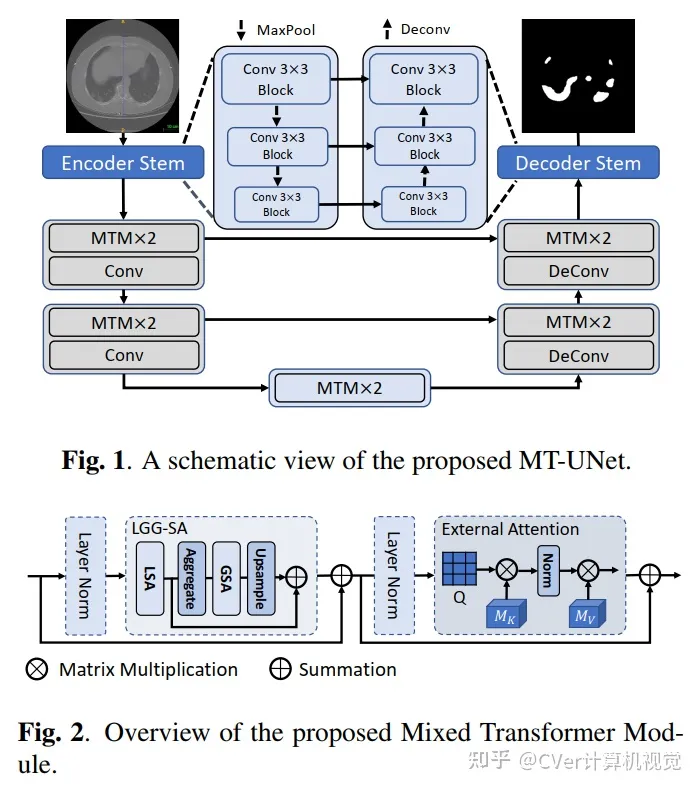

《Mixed Transformer U-Net For Medical Image Segmentation》